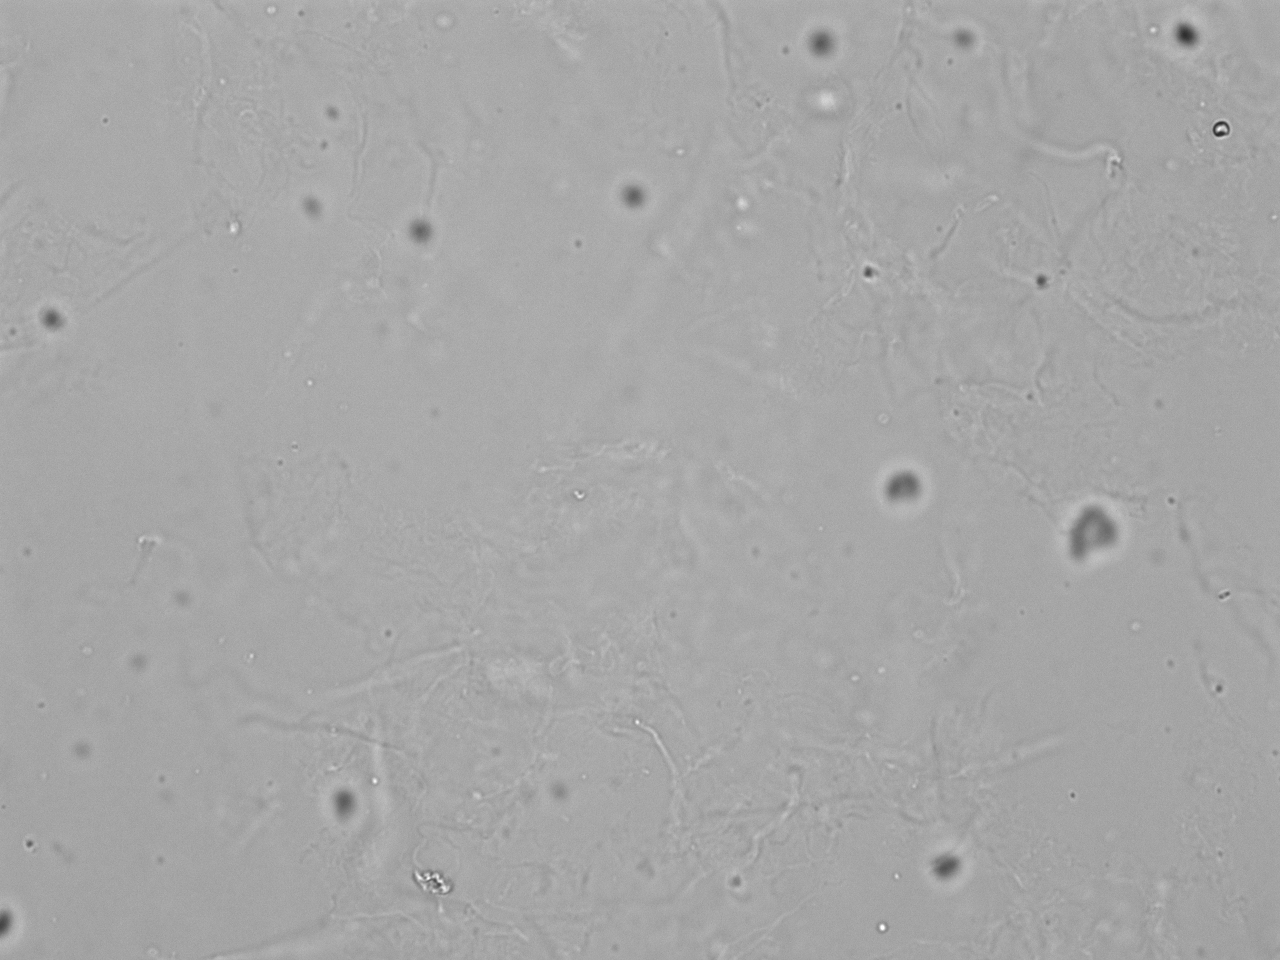

Probe mit leichter Leukozyturie und Mikrohämaturie; Bildmaterial für Explorer-Demo.

Mikroskopie-Bilder